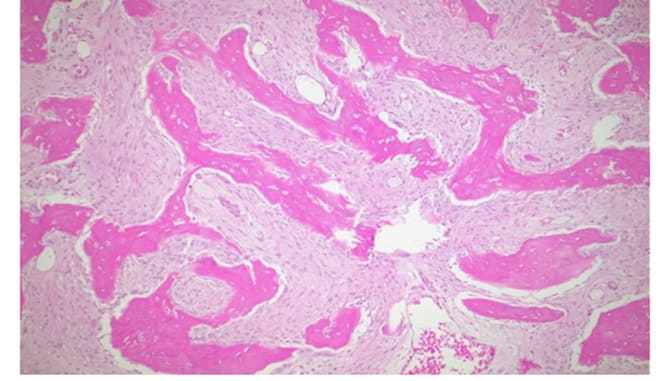

Histopathological Features:

Figure 10: H&E, 25X,: Irregular and curvilinear arrangement of trabeculae.